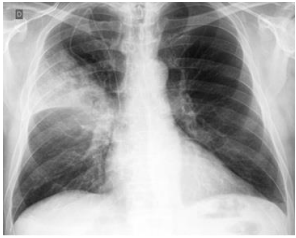

Observe a imagem abaixo:

Podemos observar, nitidamente, nesta radiografia, um infiltrado à direita, compatível com uma consolidação lobar, o que configura: